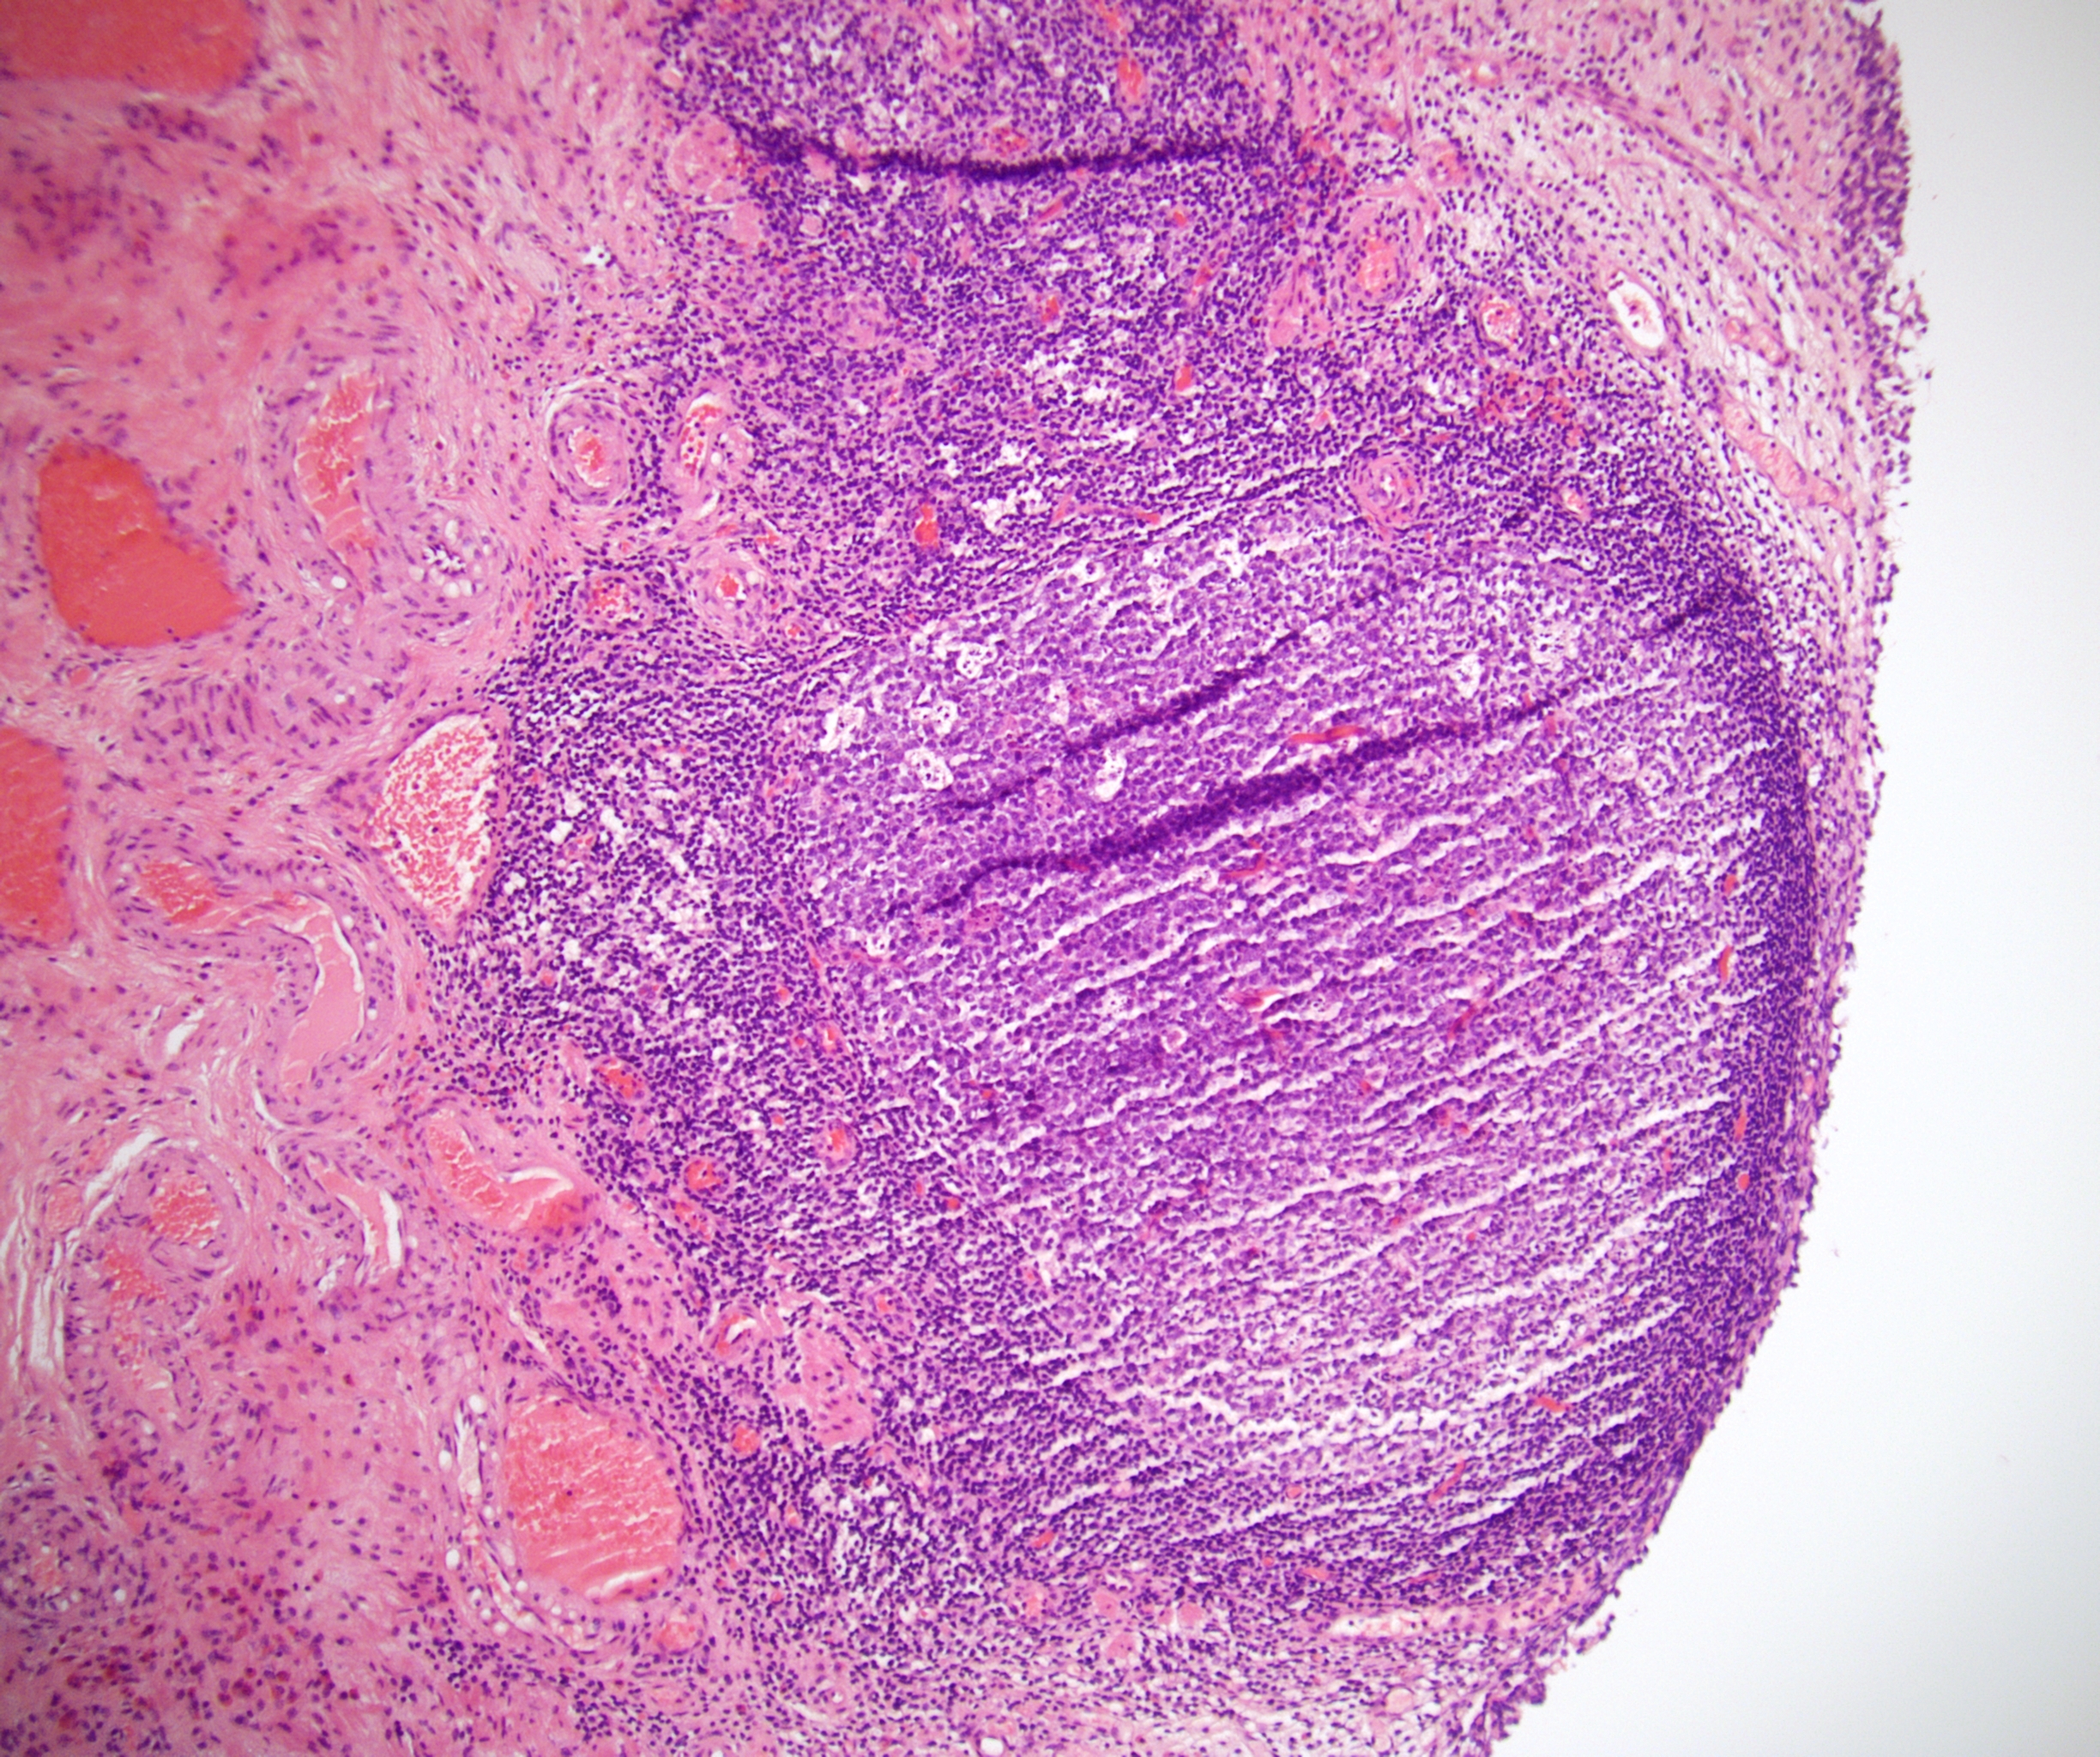

Microscopic (histologic) images

Contributed by Emily S. Reisenbichler, M.D., Andrey Bychkov, M.D., Ph.D., Maria Tretiakova, M.D., Ph.D. and Debra Zynger, M.D.